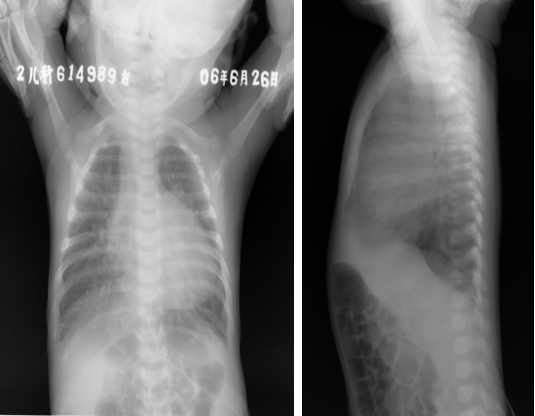

完全性大动脉换位:胸片表现

◇ “蛋形心”:大动脉阴影狭小,肺动脉略凹陷,心蒂小

◇ 心影进行性增大

◇ 肺纹理增多若伴肺动脉狭窄则肺纹理减少